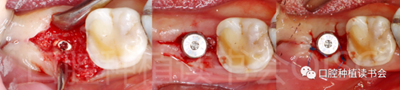

5.3.9 術(shù)后第6周,47行種植2期手術(shù),可見種植體周圍愈合良好,牙齦成型后,旋入愈合基臺(tái)(圖22)。

圖22 種植體周圍獲得了良好的骨整合。

5.4.3 術(shù)后第10周,47戴入最終種植冠,X片確認(rèn)基臺(tái)就位準(zhǔn)確(圖25),以30N.cm扭矩旋緊基臺(tái)螺絲(圖26)。

5.4.4 種植冠封閉螺絲孔后,調(diào)合,拋光,完成最終修復(fù)(圖27);戴牙前CBCT顯示:種植體頰側(cè)骨板厚度為2.88mm;47種植冠獲得了良好的穿齦輪廓,并維持了正常的頰側(cè)牙弓輪廓。